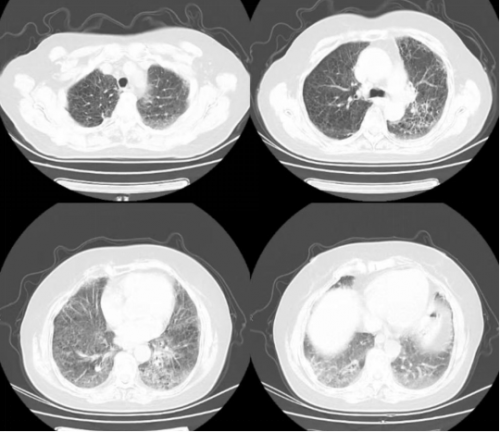

CT 影像:11 月 27 日复查胸部 CT,可见双肺磨玻璃渗出影明显吸收,对比 11 月 18 日影像,肺部病变改善显著。

11月27日肺CT:

11月18日肺部 CT

11月27日肺部CT

患者肺部影像学提示双肺间质纤维化伴磨玻璃样渗出影,考虑慢性纤维化性间质性肺病伴急性感染,患者高龄、免疫低下,给予呼吸支持的同时积极抗细菌、抗机会性感染。入院时血气提示I型呼吸衰竭,结合影像表现符合急性呼吸窘迫综合征,在基础治疗的同时应积极对抗全身炎症反应,西维来司他钠作为核心抗炎抗纤维化药物,它的应用是本次治疗的关键。其独特机制可针对性抑制肺部炎症反应和纤维化进展,与尼达尼布存在协同作用。避免了长期大剂量激素带来的血糖升高、感染风险增加等不良反应,符合当前间质性肺病治疗中 “减少激素依赖” 的趋势。从治疗效果来看,患者炎症指标快速下降、肺部病变显著吸收,证实了该药物在慢性纤维化性间质性肺病急性加重中的重要作用,尤其适用于非感染性炎症主导的病情进展。但西维来司他钠与尼达尼布联合使用的协同机制尚需更深入的基础研究验证,是否可根据患者具体表型调整剂量或用药时长,以达到更优治疗效果仍需讨论。